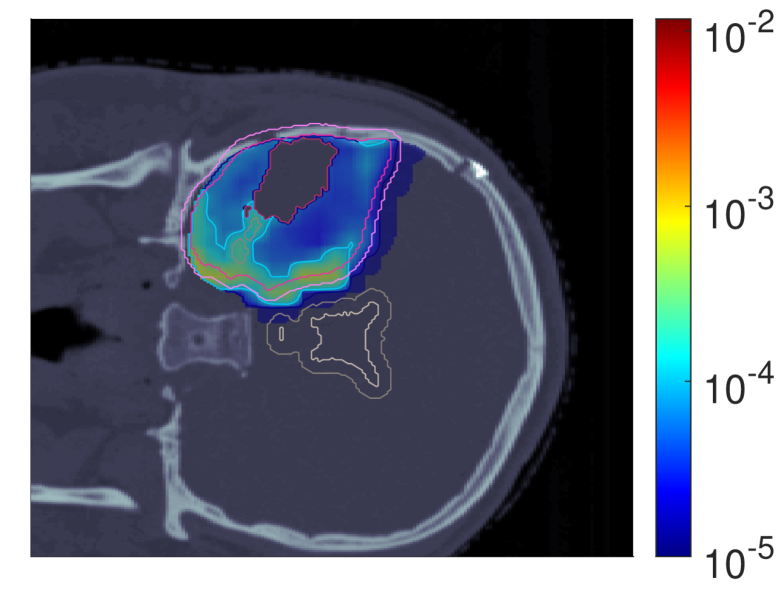

Figure 3 shows the slice images with the optimal dose distributions, where the POLO model-based objective functions are displayed vertically and the NTCP levels horizontally.

NTCP30 %NTCP\approx{$30\text{\,}\mathrm{\char 37\relax}$} NTCP20 %NTCP\approx{$20\text{\,}\mathrm{\char 37\relax}$} NTCP10 %NTCP\approx{$10\text{\,}\mathrm{\char 37\relax}$}

dRBE,fxd_{RBE,fx} (NTCPp)(NTCP_{p})

Refer to caption Refer to caption Refer to caption

dRBE,fxd_{RBE,fx} (LSEp~)(LSE_{\tilde{p}})

dRBE,fxd_{RBE,fx} (H~p)(\tilde{H}_{p})

dRBE,fxd_{RBE,fx} (H~p~)(\tilde{H}_{\tilde{p}})

Figure 3: Optimal slice images of the RBE-weighted fractional dose dRBE,fxd_{RBE,fx} (in Gy\mathrm{Gy}(RBE)) for NTCPpNTCP_{p}, LSEp~LSE_{\tilde{p}}, H~p\tilde{H}_{p} and H~p~\tilde{H}_{\tilde{p}} at different NTCP levels. The objective functions behave similarly in that dose is reduced to achieve a lower NTCP value. However, they differ in the strength of the dose reduction inside and the impact on the dose outside the target volume, particularly in the VS. NTCPpNTCP_{p} and H~p\tilde{H}_{p} show comparable dose results, while LSEp~LSE_{\tilde{p}} and H~p~\tilde{H}_{\tilde{p}} more aggressively eliminate dose in the target volume.

We observe intra-functional similarities of the objectives from a reduction of the dose values with decreasing NTCP level, especially in the overlapping regions to the VS, but also within the target volumes. NTCPpNTCP_{p} manages to reduce the risk estimate by almost 26 %26\text{\,}\mathrm{\char 37\relax} compared to the baseline plan without affecting target coverage (ΔPTVd95RBE,fx0.03\Delta_{\text{PTV}}\text{d95}_{RBE,fx}\approx{0.03}, ΔGTVd95RBE,fx0.001\Delta_{\text{GTV}}\text{d95}_{RBE,fx}\approx{0.001}), which can be attributed to the dose contraction away from the VS. This is even more pronounced when lowering the NTCP level to 10 %10\text{\,}\mathrm{\char 37\relax}, but is then accompanied by a loss in target coverage (ΔPTVd95RBE,fx0.07\Delta_{\text{PTV}}\text{d95}_{RBE,fx}\approx{0.07}, ΔGTVd95RBE,fx0.02\Delta_{\text{GTV}}\text{d95}_{RBE,fx}\approx{0.02}).

From an inter-functional perspective H~p\tilde{H}_{p} seems to behave very similarly, with only minor deviations in the dose slice. In contrast, we find that LSEp~LSE_{\tilde{p}} and H~p~\tilde{H}_{\tilde{p}} modulate the dose more strongly, with local inhomogeneities already at an NTCP level of 30 %30\text{\,}\mathrm{\char 37\relax}. Here, LSEp~LSE_{\tilde{p}} only marginally reduces the dose in the upper part of the VS but restricts the dose exposure in the target volume (ΔPTVd95RBE,fx0.26\Delta_{\text{PTV}}\text{d95}_{RBE,fx}\approx{0.26}, ΔGTVd95RBE,fx0.1\Delta_{\text{GTV}}\text{d95}_{RBE,fx}\approx{0.1}). Even more, target coverage breaks down at an NTCP level of 10 %10\text{\,}\mathrm{\char 37\relax} (ΔPTVd95RBE,fx0.51\Delta_{\text{PTV}}\text{d95}_{RBE,fx}\approx{0.51}, ΔGTVd95RBE,fx0.24\Delta_{\text{GTV}}\text{d95}_{RBE,fx}\approx{0.24}). One reason could be the focus of LSEp~LSE_{\tilde{p}} on maximum points, causing a “notch” in the high dose region around the overlap of CTV/PTV and VS at an NTCP level of 20 %20\text{\,}\mathrm{\char 37\relax}.

H~p~\tilde{H}_{\tilde{p}}, on the other hand, results in an immediate dose contraction, with higher concentration on the GTV with lower NTCP level. Similar to LSEp~LSE_{\tilde{p}}, target coverage is drastically affected at 10 %10\text{\,}\mathrm{\char 37\relax} NTCP (ΔPTVd95RBE,fx0.71\Delta_{\text{PTV}}\text{d95}_{RBE,fx}\approx{0.71}, ΔGTVd95RBE,fx0.22\Delta_{\text{GTV}}\text{d95}_{RBE,fx}\approx{0.22}), which may be due to the increased scale of the function values and gradients of the linearly reformulated POLO model and therefore the higher impact of LSEp~LSE_{\tilde{p}} and H~p~\tilde{H}_{\tilde{p}} on the plan.